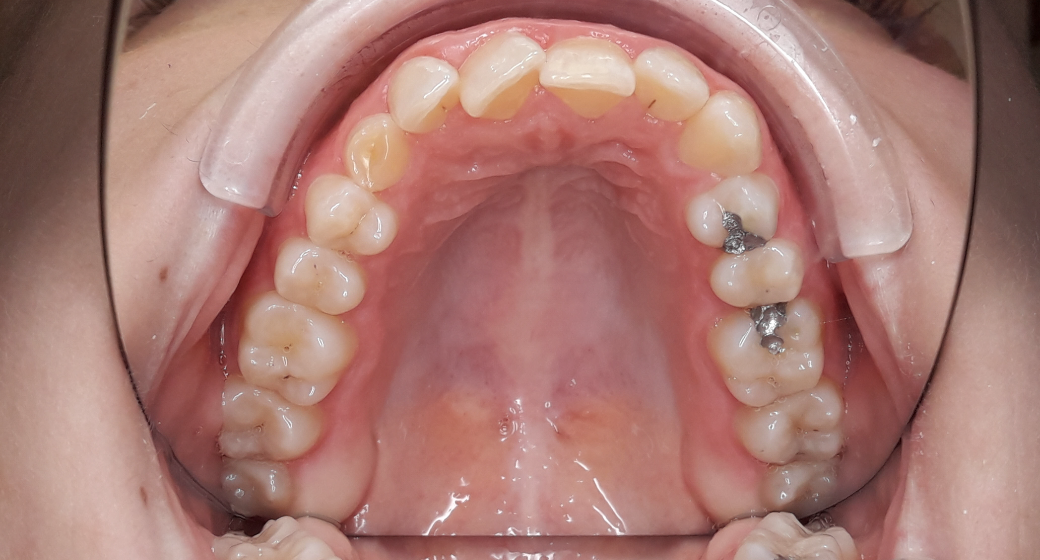

Behandlung Vorher-Nachher-Bild | Kieferorthopädie  | von Dr. Neda Yavari | Elmshorn d82c8d16 Vorher-Bild

Bei diesem Fall handelt es sich um einen verlagerten Eckzahn: Auf dem ersten Foto sieht man noch den Milchzahn, der entfernt wurde.

Der bleibende Eckzahn wurde chirurgisch freigelegt und angeschlungen, um ihn kieferorthopädisch einzuordnen - für ein schönes, gerades Lächeln.